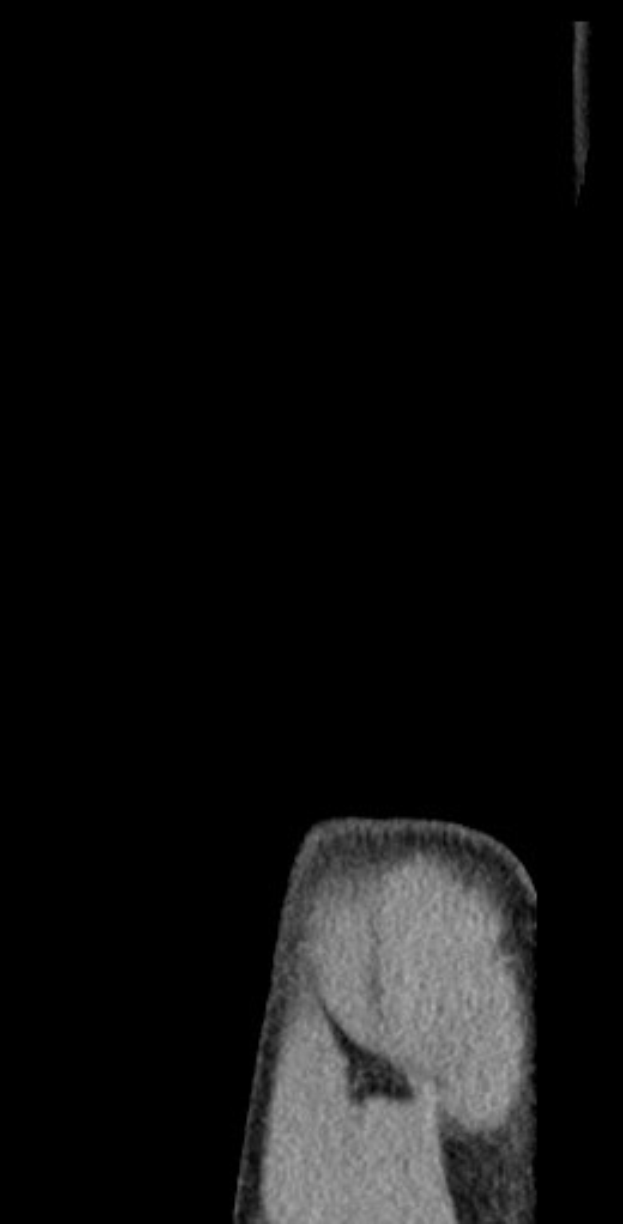

Der 21-jährige Verteidiger musste Anfang dieses Monats im EM-Qualifikationsspiel der deutschen U21 gegen Griechenland mit Schulterschmerzen ausgewechselt werden. Die Verletzung gibt Anlass zur Sorge, da sie dieselbe Schulter betrifft, die bereits im vergangenen Jahr operiert werden musste und Gechter monatelang außer Gefecht setzte.

Gechters jüngster Rückschlag ereignete sich Anfang April, als er für die deutsche U21 auflief. Das Problem tritt in derselben Schulter auf, die er sich im September 2025 zugezogen hatte und die einen chirurgischen Eingriff erforderte, gefolgt von einer langen Pause. Zwar hatte er sich vollständig erholt und sich in den letzten Monaten einen Stammplatz in der Innenverteidigung von Hertha erkämpft, doch die erneuten Beschwerden werfen nun Fragen über seinen Einsatz auf.

Eine MRT-Untersuchung soll das Ausmaß der Verletzung klären, doch bisher liegt weder eine offizielle Diagnose noch ein Behandlungsplan vor. Angesichts des anstehenden Spiels gegen Dresden könnte Trainer Stefan Leitl gezwungen sein, seine Abwehr umzustellen. Als mögliche Ersatzkandidaten gelten Pascal Klemens und Toni Leistner, falls Gechter nicht rechtzeitig fit wird.